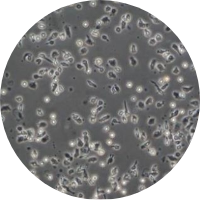

具体的には、患者さんの血液をお預かりして血液中に含まれる免疫細胞を2~3週間程度培養し、細胞を活性化させて再び体内に戻します。

採取した血液は細胞培養加工施設へ送られ、免疫細胞を取り出して約2~3週間かけて治療用細胞に加工します。できあがった細胞は治療日当日に当院に送られ、患者さんに投与されます。